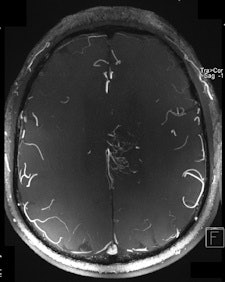

| Two 7-tesla images of a glioblastoma patient. Left: T2-weighted image shows brain lesion with very high spatial resolution. The heterogeneity in the lesion is already visible. Right: Time-of-flight MR angiogram shows the arterial vessels at the periphery of the lesion. The irregular vessel structure indicates neoangiogenesis, and it would be very interesting to see whether this vascular structure changes under new forms of neoangiogenic therapy. Image courtesy of Dr. Michael Bock. |

"High-resolution MRI in the brain, and in other anatomical areas (e.g., the knee), will become the first established clinical applications of high-field MRI," he said. "For example, we are able to visualize the tiny neovasculature in brain tumors, so high-field MRI might be a powerful tool to assess therapy response to the more and more popular neoangiogenic treatment," he commented.

Operating at increased magnetic fields makes it easier to obtain T2* contrast-enhanced images and improved implementation of susceptibility-weighted imaging, in which the phase of gradient-echo images provides information about local variation of magnetic susceptibility, according to Richard Bowtell, a professor from the Magnetic Resonance Centre, School of Physics and Astronomy, at the University of Nottingham in the U.K. In the brain, such variation appears to be dominated by differences in iron concentration and myelin content, so that high-field SWI may provide useful information about the progression of neurodegenerative disease. The elevated T1 relaxation times at 7-tesla also offer benefits for arterial spin labeling and time-of-flight angiography.